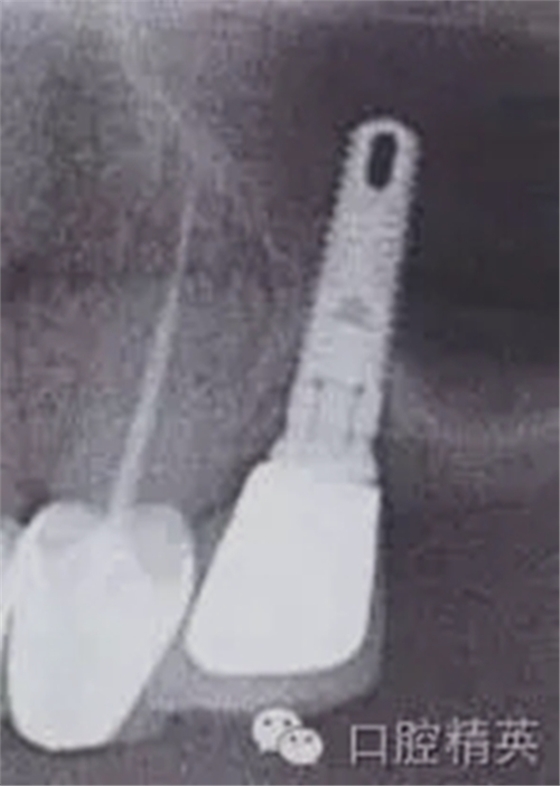

圖4:兩維曲面斷層影像難以獲得精確定位,有的醫(yī)生為了避免損傷下頜神經(jīng)管而應(yīng)用短種植體。這樣做的結(jié)果是增加了修復(fù)體-種植體長(zhǎng)度比,隨著時(shí)間的流逝會(huì)造成骨吸收,最終可能導(dǎo)致種植體折斷。骨內(nèi)折斷的種植體片斷需要手術(shù)取出,然后進(jìn)行植骨,骨質(zhì)愈合后再次種植,這些步驟不僅創(chuàng)傷大,而其從心理和經(jīng)濟(jì)上都會(huì)對(duì)患者造成損失。

如這個(gè)病例展示的,CBCT斷層掃描揭示了牙槽骨根方的凹陷。這樣就避免了術(shù)中的意外,醫(yī)生可以在術(shù)前完善的計(jì)劃,向患者交代清楚手術(shù)方法、風(fēng)險(xiǎn)、以及植骨所需增加的相應(yīng)費(fèi)用等問(wèn)題。在兩維的放射影像中是無(wú)法預(yù)先觀察到這個(gè)問(wèn)題的。僅使用兩維放射診斷帶來(lái)的另一個(gè)并發(fā)癥是種植體折斷。(圖4)前面提過(guò),兩維曲面斷層影像難以獲得精確定位,有的醫(yī)生為了避免損傷下頜神經(jīng)管而應(yīng)用短種植體。這樣做的結(jié)果是增加了修復(fù)體-種植體長(zhǎng)度比,隨著時(shí)間的流逝會(huì)造成骨吸收,最終可能導(dǎo)致種植體折斷。

這種情況發(fā)生時(shí),骨內(nèi)折斷的種植體片斷需要手術(shù)取出,然后進(jìn)行植骨,骨質(zhì)愈合后再次種植,這些步驟不僅創(chuàng)傷大,而其從心理和經(jīng)濟(jì)上都會(huì)對(duì)患者造成損失。關(guān)于修復(fù)體—種植體高度比的問(wèn)題也常導(dǎo)致修復(fù)醫(yī)生和外科醫(yī)生之間的爭(zhēng)執(zhí)。我們將在后面關(guān)于物理機(jī)械原因?qū)е碌姆N植體失敗模式的章節(jié)中進(jìn)一步討論關(guān)于修復(fù)“冠根”比的概念。